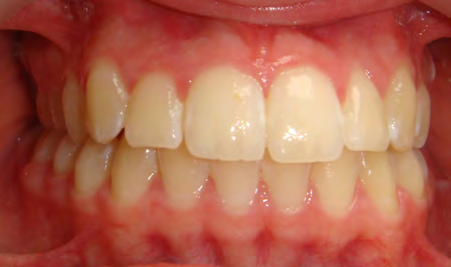

Below are cases treated at Vakresmil without extractions within the last three years. The families had been told, “It is simply not possible for your child to be treated without extractions” by orthodontists. Judge for yourself if that was right or wrong.

The overall aim is to produce the best smile we can — a “beautiful smile”, if you will — without premolar extractions, headgear, facemasks or banded appliances. A smile that both the patient and we at Vakresmil can be proud of.